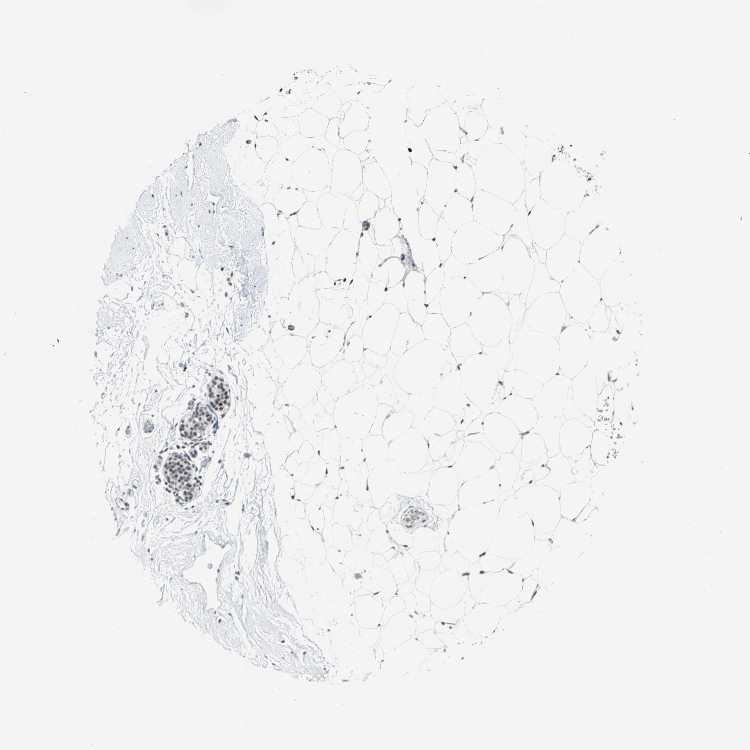

BREAST - Antibody stainingi

Antibody staining in the annotated cell types in the current human tissue is reported as not detected, low, medium, or high, based on conventional immunohistochemistry profiling in selected tissues. This score is based on the combination of the staining intensity and fraction of stained cells.

Each image is clickable and will lead to virtual microscopy that enables deeper exploration of all samples and also displays staining intensity scores, fraction scores and subcellular localization as well as patient and tissue information for each sample.

Antibody HPA004911

Adipocytes Not detected

Glandular cells Medium

Myoepithelial cells Not detected